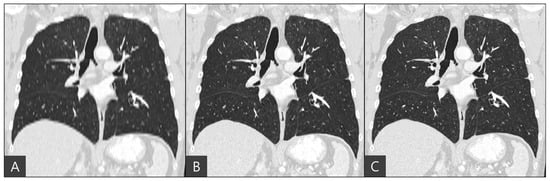

The representative coronal views of thick-slice, generated thin-slice, and ground truth thin-slice CT images are presented in Figure 4. The thick-slice CT image exhibits staircase artifacts, unidentifiable fissures, and blurred lung vessels, whereas the generated thin-slice CT image quality is comparable to that of the ground truth thin-slice CT image. Visual inspection of GGN and solid nodules in each image type reveals clearer distinctions. In Figure 5, the GGN in the thick slice CT image has indistinct boundaries, making accurate segmentation and volume estimation challenging. In contrast, the GGN in the generated thin-slice CT image closely resembles that in the ground truth thin-slice CT image, facilitating accurate assessment. The Likert scale scored 1, 4, 5 on the visibility of fine lung structures, 1, 4, 5 on nodule margin delineation, and 1, 4, 5 on visibility of GGN/subsolid nodule component for thick-slice, generated thin-slice, and thin-slice CT, respectively, by both radiologists. Similarly, for solid nodules, the thick-slice CT image lacks sufficient image quality for precise volume measurement, whereas the solid nodule in the generated thin-slice CT image exhibits adequate quality for accurate segmentation, mirroring the ground truth. The Likert scale scored 1, 4, 5 on the visibility of fine lung structures and 1, 4, 5 on nodule margin delineation for the thick-slice, generated thin-slice, and thin-slice CT, respectively, by both radiologists.

Figure 4. Coronal view of (A) thick-slice, (B) generated thin-slice and (C) thin-slice CT images.